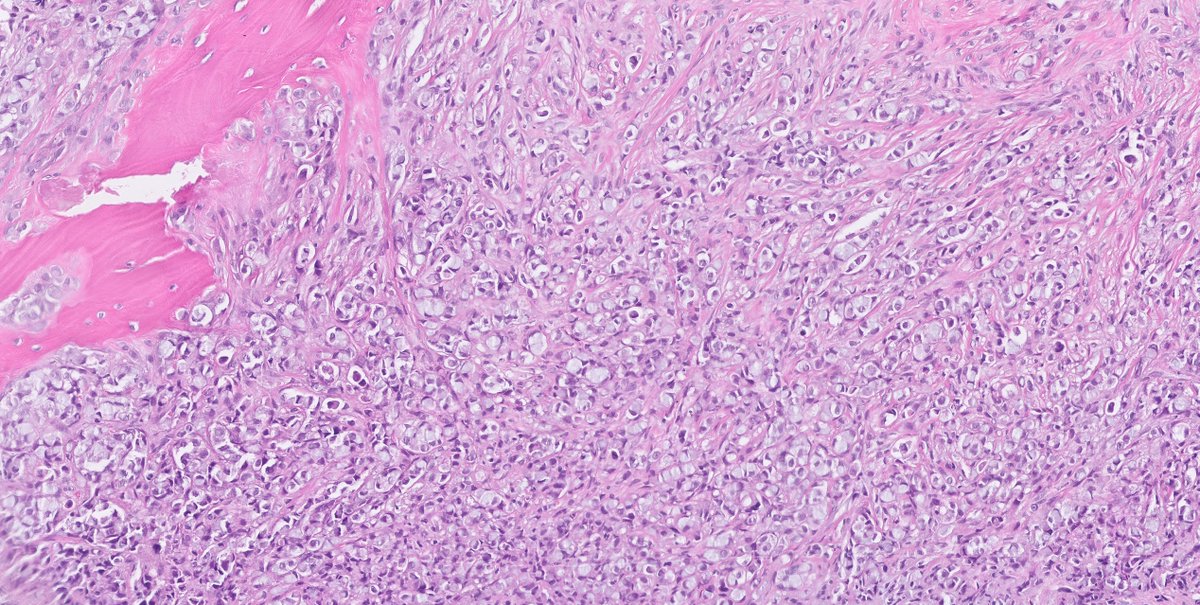

1/ #PathTwitter what is your understating on this skeletal metastasis in an elderly female?

2/ #CUP

7/ So indeed this was a metastatic breast carcinoma and the answer and the problem lies in the non-specificity of the SP24 antibody as highlighted buy several of you

more specifically metastatic lobular carcinoma